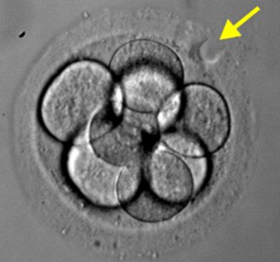

ÕĤÕÅæµĆ¦µŚĀń▓ŠńŚćµéŻĶĆģĶ¦ŻÕå│Ķ«ĪÕłÆ